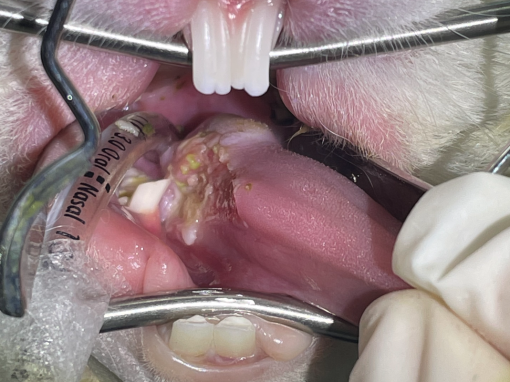

Photo reference: